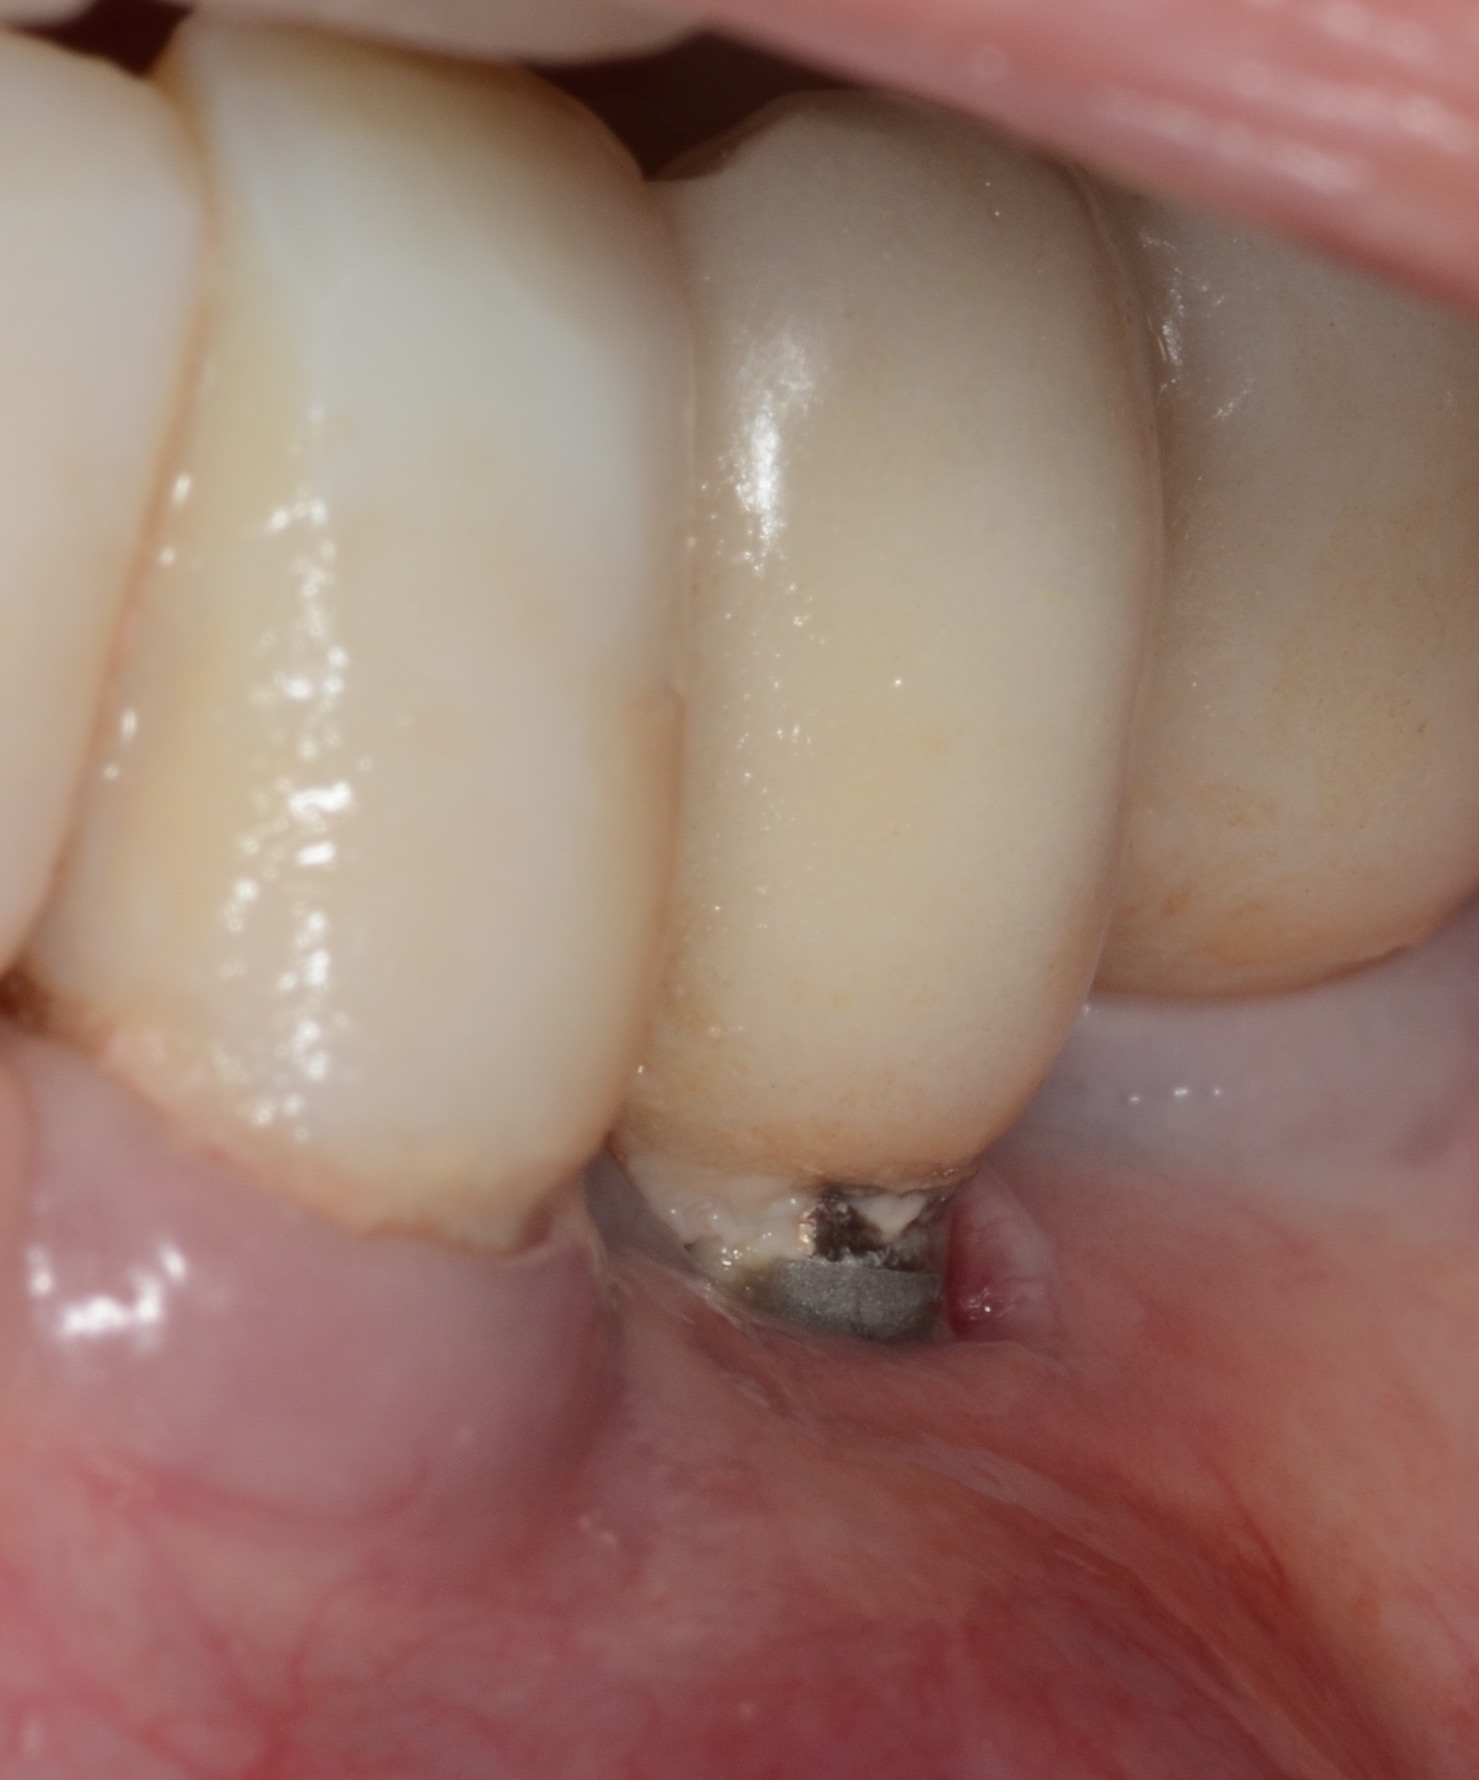

According to the European Association for Osseointegration's third Consensus Conference in 2012, 63% of patients with implants experience peri-implant mucositis, and one in five of these patients will develop peri-implantitis within 5 years of placement.2 Peri-implantitis is an inflammatory condition that develops as a response to bacteria lingering around the neck of the implant. Froum and Rosen defined peri-implantitis as peri-implant disease that has progressed beyond gingivitis or peri-implant mucositis to the point of bone loss.3 This bone loss is best identified on periapical radiographs, where the crestal bone and implant threads are clearly visualized (Figure 1). Oftentimes, computed tomography (CT) scans produce scatter radiation that can interfere with clear identification of bone loss at the neck of the implant.

(1.) Periapical x-ray image showing clear demarcation of implant threads and visible bone loss characteristic of peri-implantitis.

Figure 1